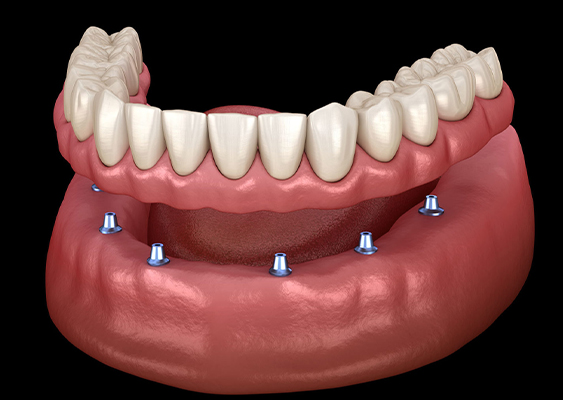

Implants replace a portion of the tooth root, creating a more natural connection with the jawbone. Through osseointegration, the titanium in the implant fuses with the jawbone, promoting long-term dental health by stimulating and strengthening the bone. In contrast, traditional dentures can lead to jawbone deterioration, while implants provide a stronger and healthier jawbone by replacing the root.

Full arch implants offer a comfortable and natural feel for your mouth and jaw, allowing you to carry on with your daily activities without the need for constant maintenance like traditional dentures. Your new teeth will blend seamlessly with your natural teeth, making it difficult for others to distinguish between them. Transitioning to full arch implants is also quicker and more natural compared to dentures.